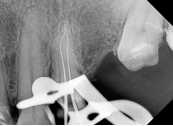

1. Negociación inicial y permeabilización con limas manuales (#06 a #10)

Se inició con limas manuales de calibre #06 hasta #10, empleando movimientos suaves de exploración y balance de fuerzas.

Este paso crítico tiene como objetivo principal permeabilizar el conducto y reducir el riesgo de bloqueo apical.

En conductos radiculares con curvaturas severas y atresias, esta técnica manual permite una evaluación táctil precisa de la anatomía, evitando fuerzas excesivas que podrían generar transporte apical o escalones.

La permeabilización inicial establece las bases para un acceso seguro al ápice, preservando la integridad del sistema de conductos.